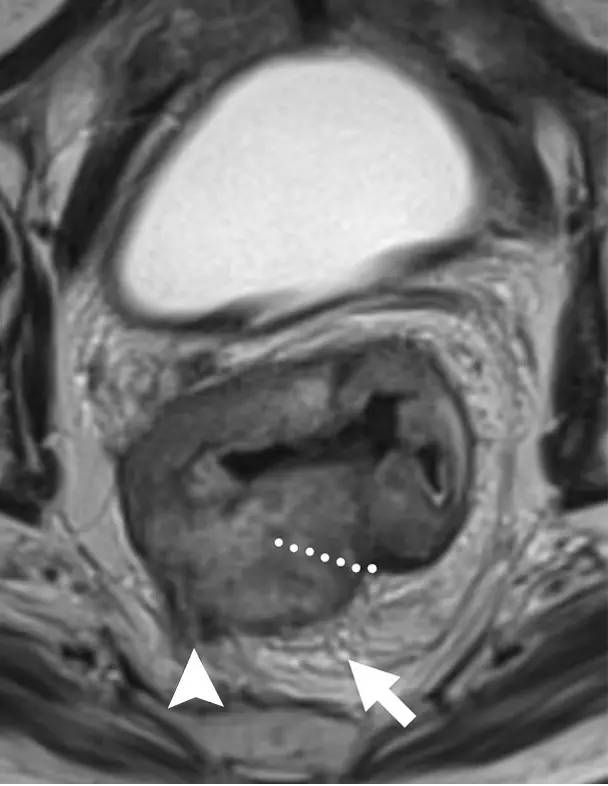

图 14 轴向 T2 加权图像上,沿着内脏腹膜有肿瘤向内生长(箭头)

图 15 同一患者腹膜转移的矢状图(箭头),在直肠内还有可疑的淋巴结